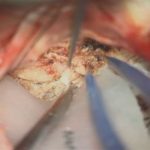

528

'24年5月

40代

脳室内腫瘍

頭蓋内腫瘍摘出術

No.’24_30 摘出 前

No.’24_30  摘出 中

No.’24_30 摘出 後